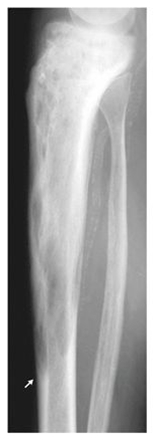

- Mistænkes ved flere målinger af forhøjet knoglespecifik alkalisk fosfatase og lokaliseret forgrovet knogletegning på røntgen eller anden billeddiagnostisk undersøgelse